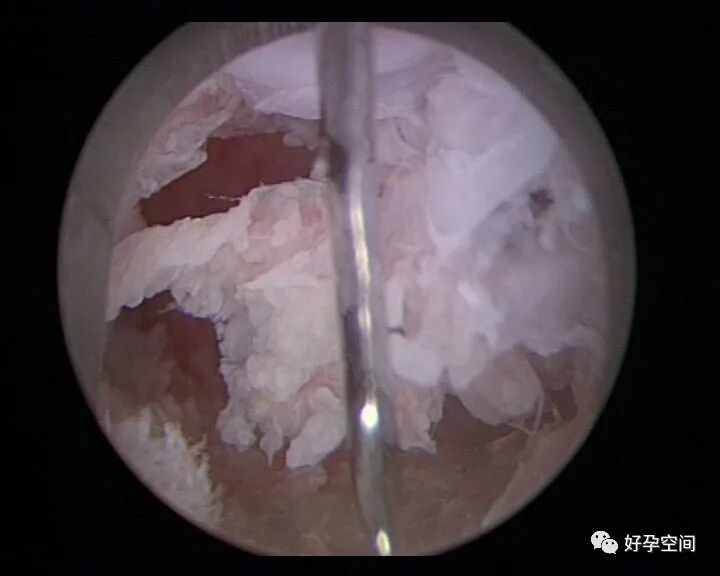

病例17:片状干酪样坏死组织